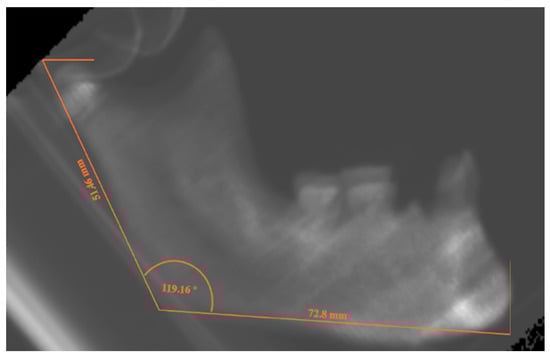

The .dcm files obtained by the CT scanning were processed with the open-source software Blue Sky Plan 4 (Blue Sky Bio Inc., Libertyville, IL, USA), which facilitated the implementation of a measurement protocol. Specifically, it was possible to build a latero-lateral radiograph for each of the mandibles. For each one, the following anatomical landmarks were identified: (a) Pogonion (the most anterior and prominent point of the horizontal ramus, Point P); (b) Gonion (Mandibular angle, the point of transition between the lower edge of the horizontal ramus and the vertical ramus), Point G; (c) Superior margin of the condyle (identified by the plane passing through the upper border of the condyle and parallel to the lower edge of the mandible), Point C. From the intersection between the plane passing through Point C and that passing through Point G and the posterior edge of the vertical ramus, Point C^1 is derived.

Once the landmarks were identified, the following segments were measured in millimeters: PG, from Pogonion to Gonion; PC^1, from Pogonion to Point C^1.

To measure the divergence between the vertical and horizontal branches of the mandible, the angle C^1-G-P was measured in degrees (Figure 2).

Figure 2. Graphical representation of the measurements taken from the latero–lateral projections. The location of each C, C^1, G, and P is referred to in the main text.

Figure 4. Latero-lateral projection of PbT12,1 mandible from the Archeo group, with the lines evoking the measurements for AR, HR and MA.